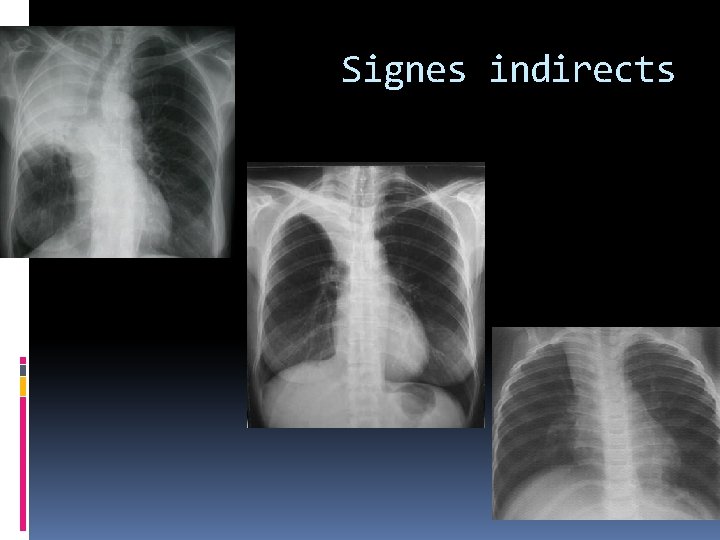

Signes indirects : Ø plus de valeur : rétraction importante et le collapsus est aéré. Ø le retentissement sur les structures anatomiques de voisinage Ces signes sont : Le déplacement et la déformation hilaire Hyperaération compensatrice des territoires normalement ventilés Le déplacement du médiastin et du poumon controlatéral L’ascension d’une coupole diaphragmatique Le pincement intercostal homolatéral

Les Signes indirects Attraction de la trachée L’ascension du hile droit. L’ascension de la bronche lobaire supérieure droite avec horizentalisation de la bronche souche. Le déplacement antérieur de l’orifice lobaire supérieur sur le cliché de profil. Les lobes moyen et inférieur en hyperaération compensatrice. Hernie médiastinale antérieure du poumon gauche est rare. Image de pic juxtaphrénique au niveau de la partie moyenne de la coupole en rapport avec la traction exercée par l’insertion du ligament triangulaire sur le diaphragme

Les Signes indirects: Attraction de la trachée vers la gauche L’ascension du hile gauche L’ascension de la bronche lobaire supérieure avec horizentalisation de la bronche souche la henrie postérointerne du lobe inférieur gauche Hernie médiastinale antérieure du poumon controlatérale est souvent visible Ascension modérée de la coupole diaphragmatique avec formation d’une image de pic Pincement intercostal est rare

Signes indirects attraction médiastinale et cardiaque attraction de la trachée Hile abaissé La bronche souche abaissée et la bronche lobaire inférieure verticalisée. Une hyperclareté compensatrice du lobe supérieur Surélevation modérée de la coupole pincement est rarement observé.